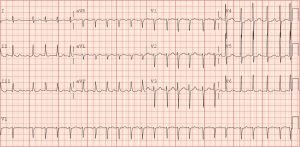

A 46-year-old male was brought in by emergency medical services (EMS) after being found unconscious outside. The patient was known to have a history of alcohol abuse and seizure disorder. No other history was available. The patient’s vital signs included a rectal temperature of 26°C, heart rate of 108, blood pressure of 124/95, respiratory rate of 14, and an oxygen saturation of 99% on a non-rebreather mask. He was unresponsive to verbal or tactile stimuli. The decision was made to intubate the patient and begin active rewarming measures. As part of his diagnostic evaluation, an EKG was obtained.

The initial EKG shows marked elevation of the J-point (point where the QRS segment joins the ST segment), otherwise known as an “Osborn Wave” (see black arrows). A subsequent EKG obtained after active rewarming, showed resolution of the Osborn waves.